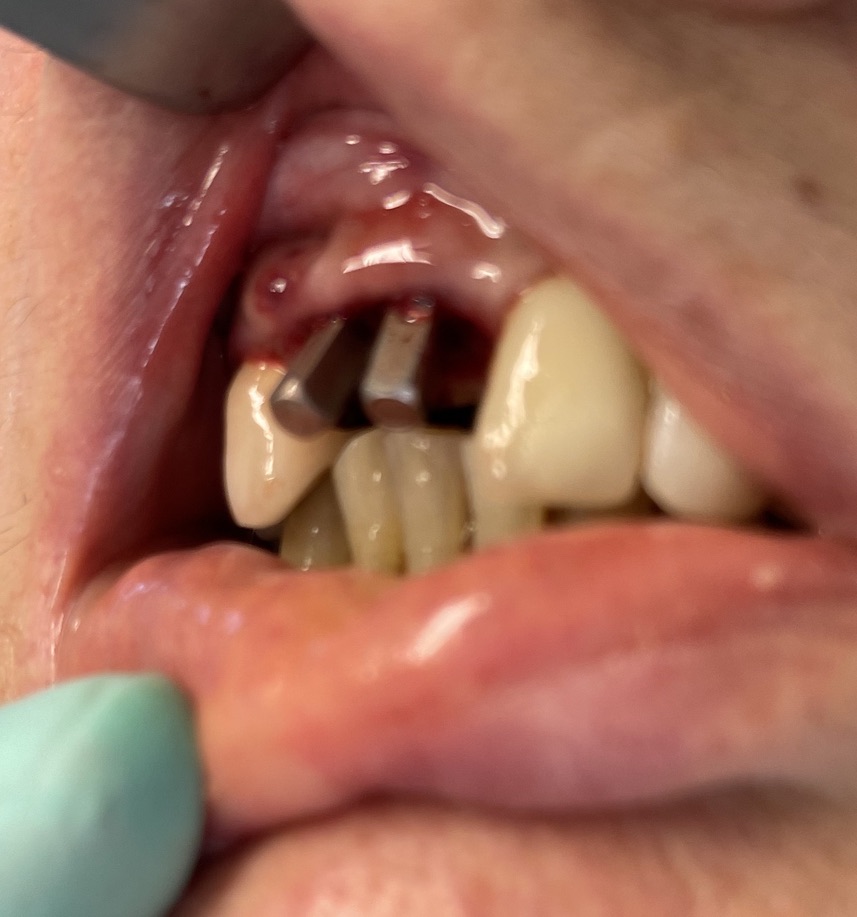

Zona dentale: 11 12

Situazione estrattiva: postestrattivi immediati

Descrizione intervento

Complicanze: assenti